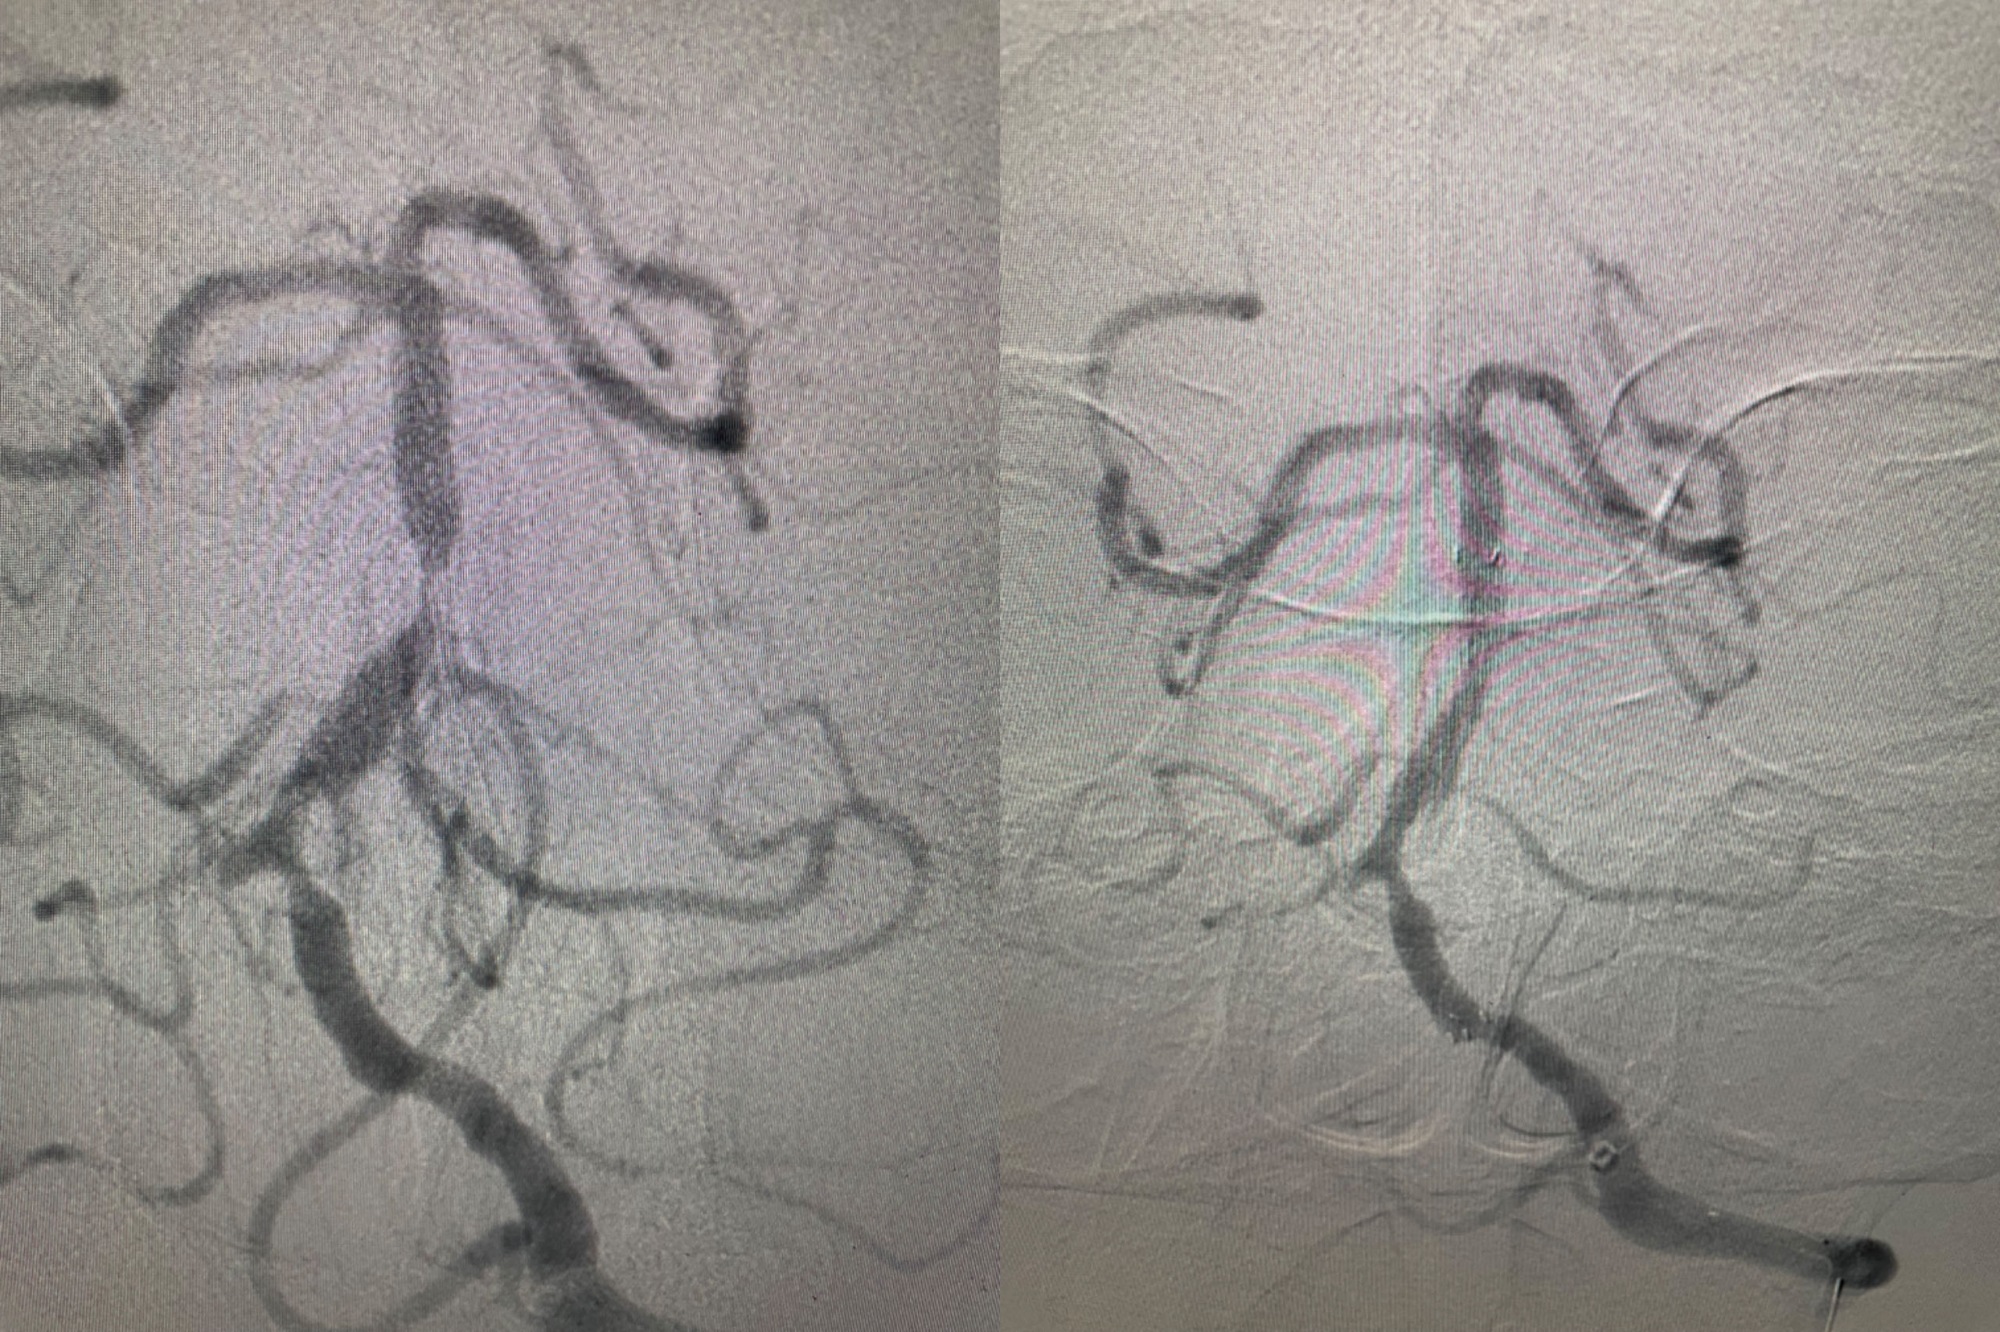

顱內血管狹窄:介入治療,球囊擴張后支架置入